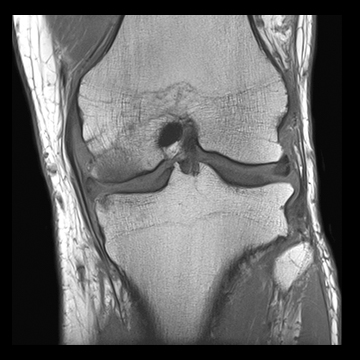

膝関節

PD 脂肪抑制

T1 TSE

3D TrueFISP脂肪抑制